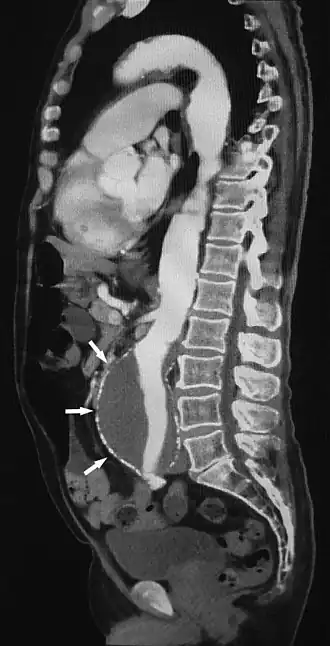

Sagittal thin slice of a computed tomography angiography abdominal aortic aneurysm (AAA) (arrows)

Aorta and great arteries

CTA can be used in the chest and abdomen to identify aneurysms in the aorta or other major blood vessels. These areas of weakened blood vessel walls that bulge out can life-threatening if they rupture. CTA is the test of choice when assessing aneurysm before and after endovascular stenting due to the ability to detect calcium within the wall.[3] Another positive of CTA in abdominal aortic aneurysm assessment is that it allows for better estimation of blood vessel dilation and can better detect blood clots compared to standard angiography.[4]

CTA is used also to identify arterial dissection, including aortic dissection in the aorta or its major branches. Arterial dissection is when the layers of the artery wall peel away from each other; this causes pain and can be life-threatening. CTA is a quick and non-invasive method of identifying dissections and can show the extent of the disease and if there is leakage.[4]